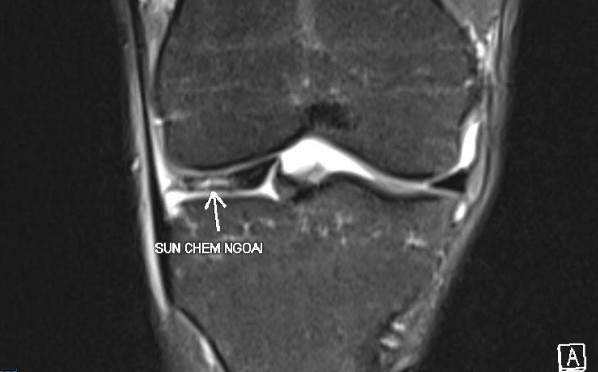

Ngoài ra, việc chơi pickleball liên tục trong thời gian dài cũng khiến nhiều người phải nhận “trái đắng”. Báo Nhân Dân đã đưa tin về trường hợp nữ bệnh nhân 32 tuổi mới chơi pickleball được 3 giờ liên tiếp thì đau khớp gối dữ dội, chụp MRI cho thấy rách sụn chêm dạng phức tạp, mảnh sụn di lệch vào trong khớp gây “kẹt gối”. Phẫu thuật nội soi được triển khai ngay để cứu phần sụn còn lại.

Hình ảnh MRI tổn thương rách sụn chêm. (Ảnh: Báo Nhân dân)